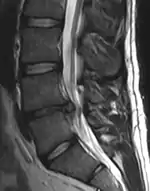

Imaging is indicated when there are red flags, ongoing neurological symptoms that do not resolve, or ongoing or worsening pain.[5] In particular, early use of imaging (either MRI or CT) is recommended for suspected cancer, infection, or cauda equina syndrome.[5] MRI is slightly better than CT for identifying disc disease; the two technologies are equally useful for diagnosing spinal stenosis.[5] Only a few physical diagnostic tests are helpful.[5] The straight leg raise test is almost always positive in those with disc herniation.[5] Lumbar provocative discography may be useful to identify a specific disc causing pain in those with chronic high levels of low back pain.[42] Similarly, therapeutic procedures such as nerve blocks can be used to determine a specific source of pain.[5] Some evidence supports the use of facet joint injections, transforminal epidural injections and sacroilliac injections as diagnostic tests.[5] Most other physical tests, such as evaluating for scoliosis, muscle weakness or wasting, and impaired reflexes, are of little use.[5]